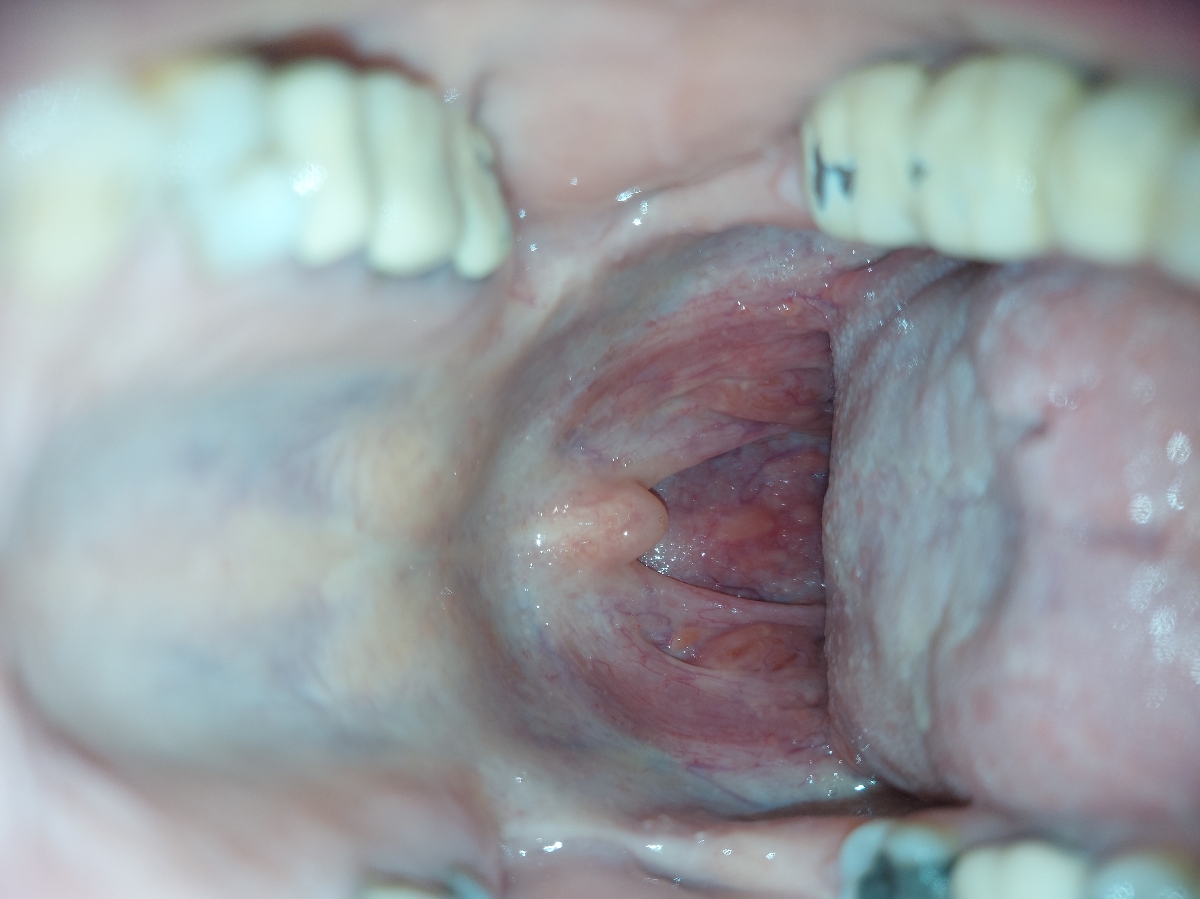

من سنگ لوزه دارم دیشب داشتم پاکشون میکردم دیدم ته حلقم این دون دونا رو داره این عکسو از اینترنت گرفتم ولی شبیه اینه خطرناکه آیا ؟؟

علت این دونه های ته حلق چی میتونه باشه؟؟

این داخل دهن خودمه 🥲

عزیزم احتمالا تحریک بافتی رخ داده شربت دیفن هیدرامین ساده در فواصل منظم قرقره کنید و بیرون بریزید تا تغییرات را ببینیم

اگر شک به hpv دارید این زگیل و hpv نیست

نه عزیزم از زگیل نمیترسم از سرطان میترسم میگم نکنه توده های ریز باشه 😑😑😅

نه جانم نترسید بنظر من تحریک بافتی است ولی باز کارهایی که گفتم انجام دهید بهتر نشد معاینه شوید خیالتان راحت شود ❤️